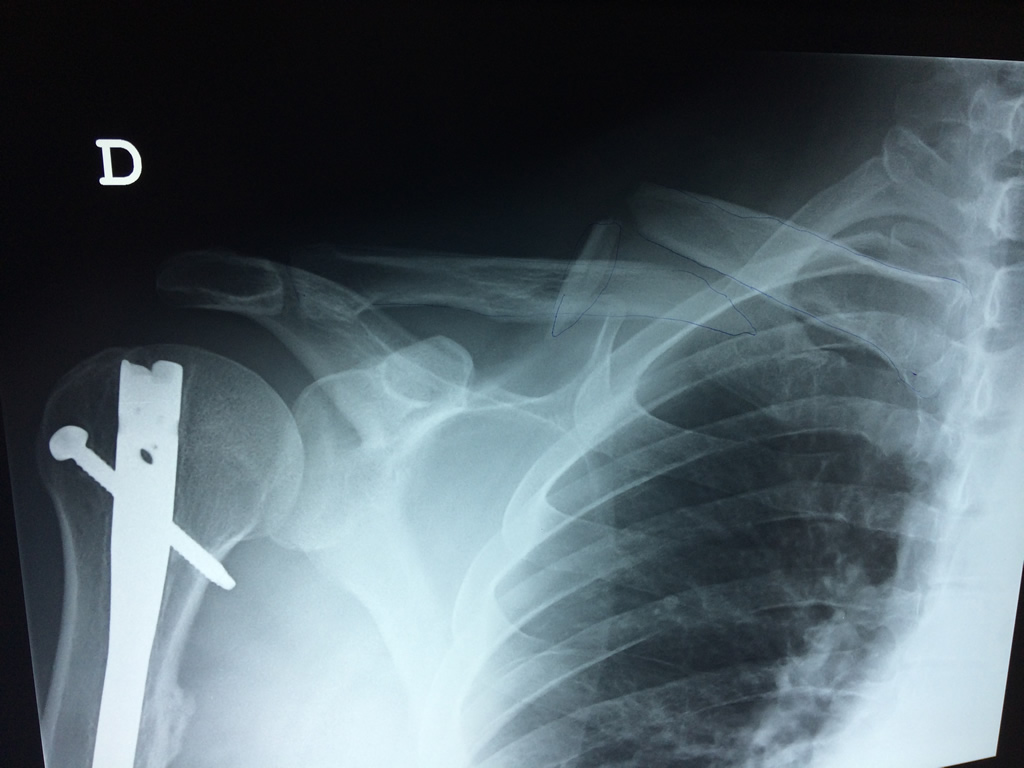

Húmero - Clavícula

La clavícula es un hueso largo, con forma de "S" itálica, situado en la parte anterosuperior del tórax. Junto con la escápula forman la cintura escapular. Se puede palpar por toda su longitud y se extiende del esternón al acromion de la escápula, siguiendo una dirección oblicua lateral y posterior.